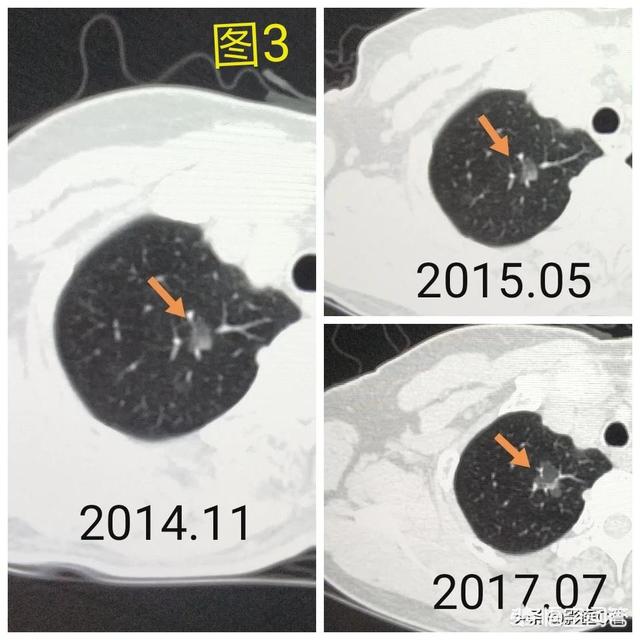

肺結節を見つけるための次のステップは、良性か悪性かを判断することである。良性の結節は、肺のリンパ節、形の悪い腫瘍、硬化性肺細胞腫など、間違いなく何でもないものである。残りの結節は良性または悪性の可能性があるもので、このような結節に対する治療の一般原則は経過観察を勧めることであり、結節の特異性(形態、大きさ、密度など)に応じて、見直しの時期は3ヵ月から1年である。結節の中には、炎症性結節のように経過観察中に吸収されて消失するものもあれば、肉芽腫のように変化しないものもあり、これは良い情報である。経過観察中に、結節の肥大、すりガラス結節の中の実成分や固形成分の増加、結節の緻密化、末梢血管が伸びているのが見えるなど、悪性の徴候があれば、積極的に対処すべきです。実際、人を見るように、正義の顔は、一般的に良い人、凶暴で悪質な悪人であり、いくつかの一時的な人の行動の観察を通じてのみ見ることができない、ルールは一般的に恐れていない場合は、悪い行動があることを発見した場合は、タイムリーに対処する必要があります。図1、左肺上部のすりガラス状の結節(オレンジ色の矢印)を発見し、2年以上経過観察したが変化なし。図2、右肺上部に2個の小さなすりガラス結節(オレンジ色の矢印)、2年後に消失した。図3、右肺上部のすりガラス状の小結節、3回目の経過観察で大きくなっているので、前向きに対処することを勧め、外科的病理検査でin situ癌、つまり前癌病変を発見すれば、肺癌の芽を摘むことができる。